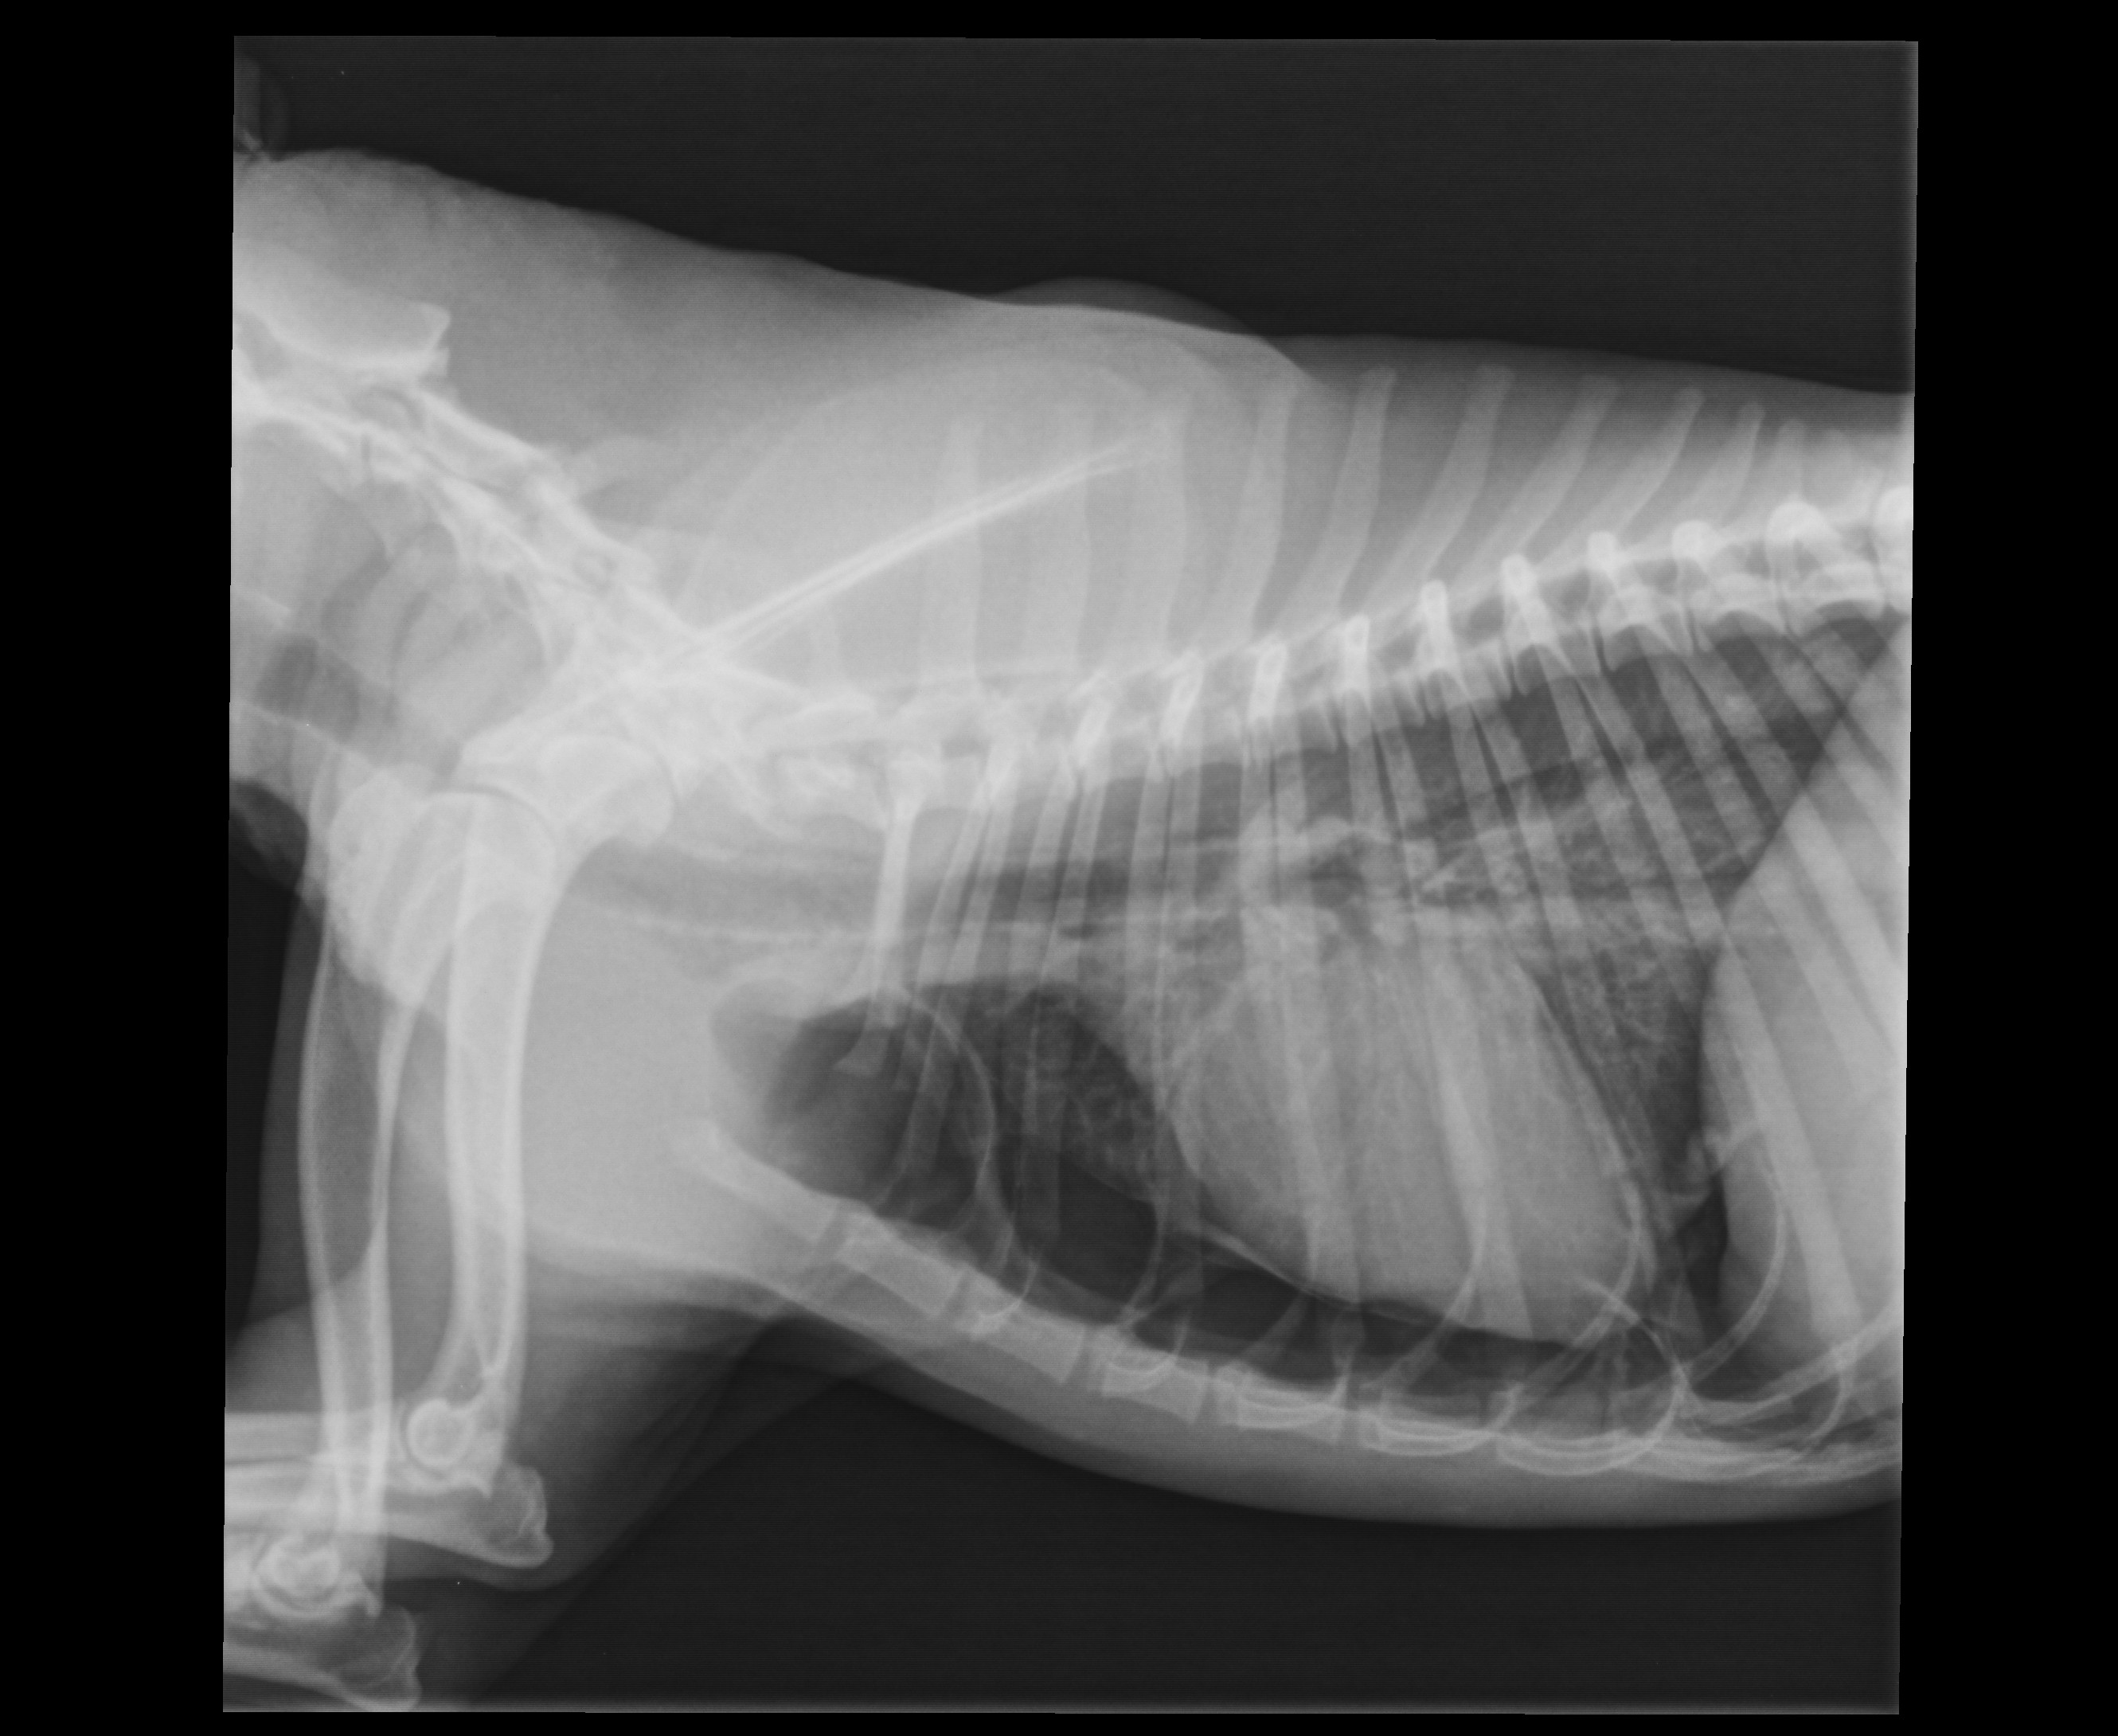

A SEAN le han hecho analitica y radiografias.

Radiografias

Se observa que tiene los pulmones perforados y el torax lleno de aire (de alli la respiración dificultosa) y para eso lo único es reposo.

Tiene la cadera fuera de su sitio y será necesario operación para cortar la cabeza del femur. Estas son las radiografías de SEAN: